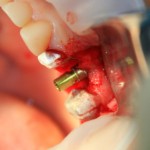

Синуслифтинг и имплантация

Конечная цель операции синуслифтинга – создание адекватных условий для установки имплантов. При этом, нередко удается провести имплантацию одновременно с операцией синуслифтинга. Как уже говорилось выше, это возможно, если существующий объем костной ткани позволяет стабилизировать имплантат заданного размера (рис 43, 44, 45):

Рисунок 43, 44, 45. Установка имплантов одномоментно с операцией синуслифтинга: слева – этап синуслифтинга, в центре – подготовка лунки под имплантат (виден спейсер и слизистая оболочка гайморовой пазухи), справа – установленный имплант

Оптимальное расстояние от дна гайморовой пазухи до верхней точки альвеолярного гребня верхней челюсти, при котором возможна стабилизация импланта длиной 10-11 мм – не менее 3-4 мм. Однако, в некоторых случаях имплантат длиной 11 мм удается стабилизировать в меньшем объеме костной ткани (рис 46, 47, 48):

Рисунок 46, 47, 48. Стабилизация импланта при толщине костной ткани менее 3 мм: слева – установка импланта после синуслифтинга, в центре – заполнение субантрального пространства спейсером, справа – рентгенологический контроль.